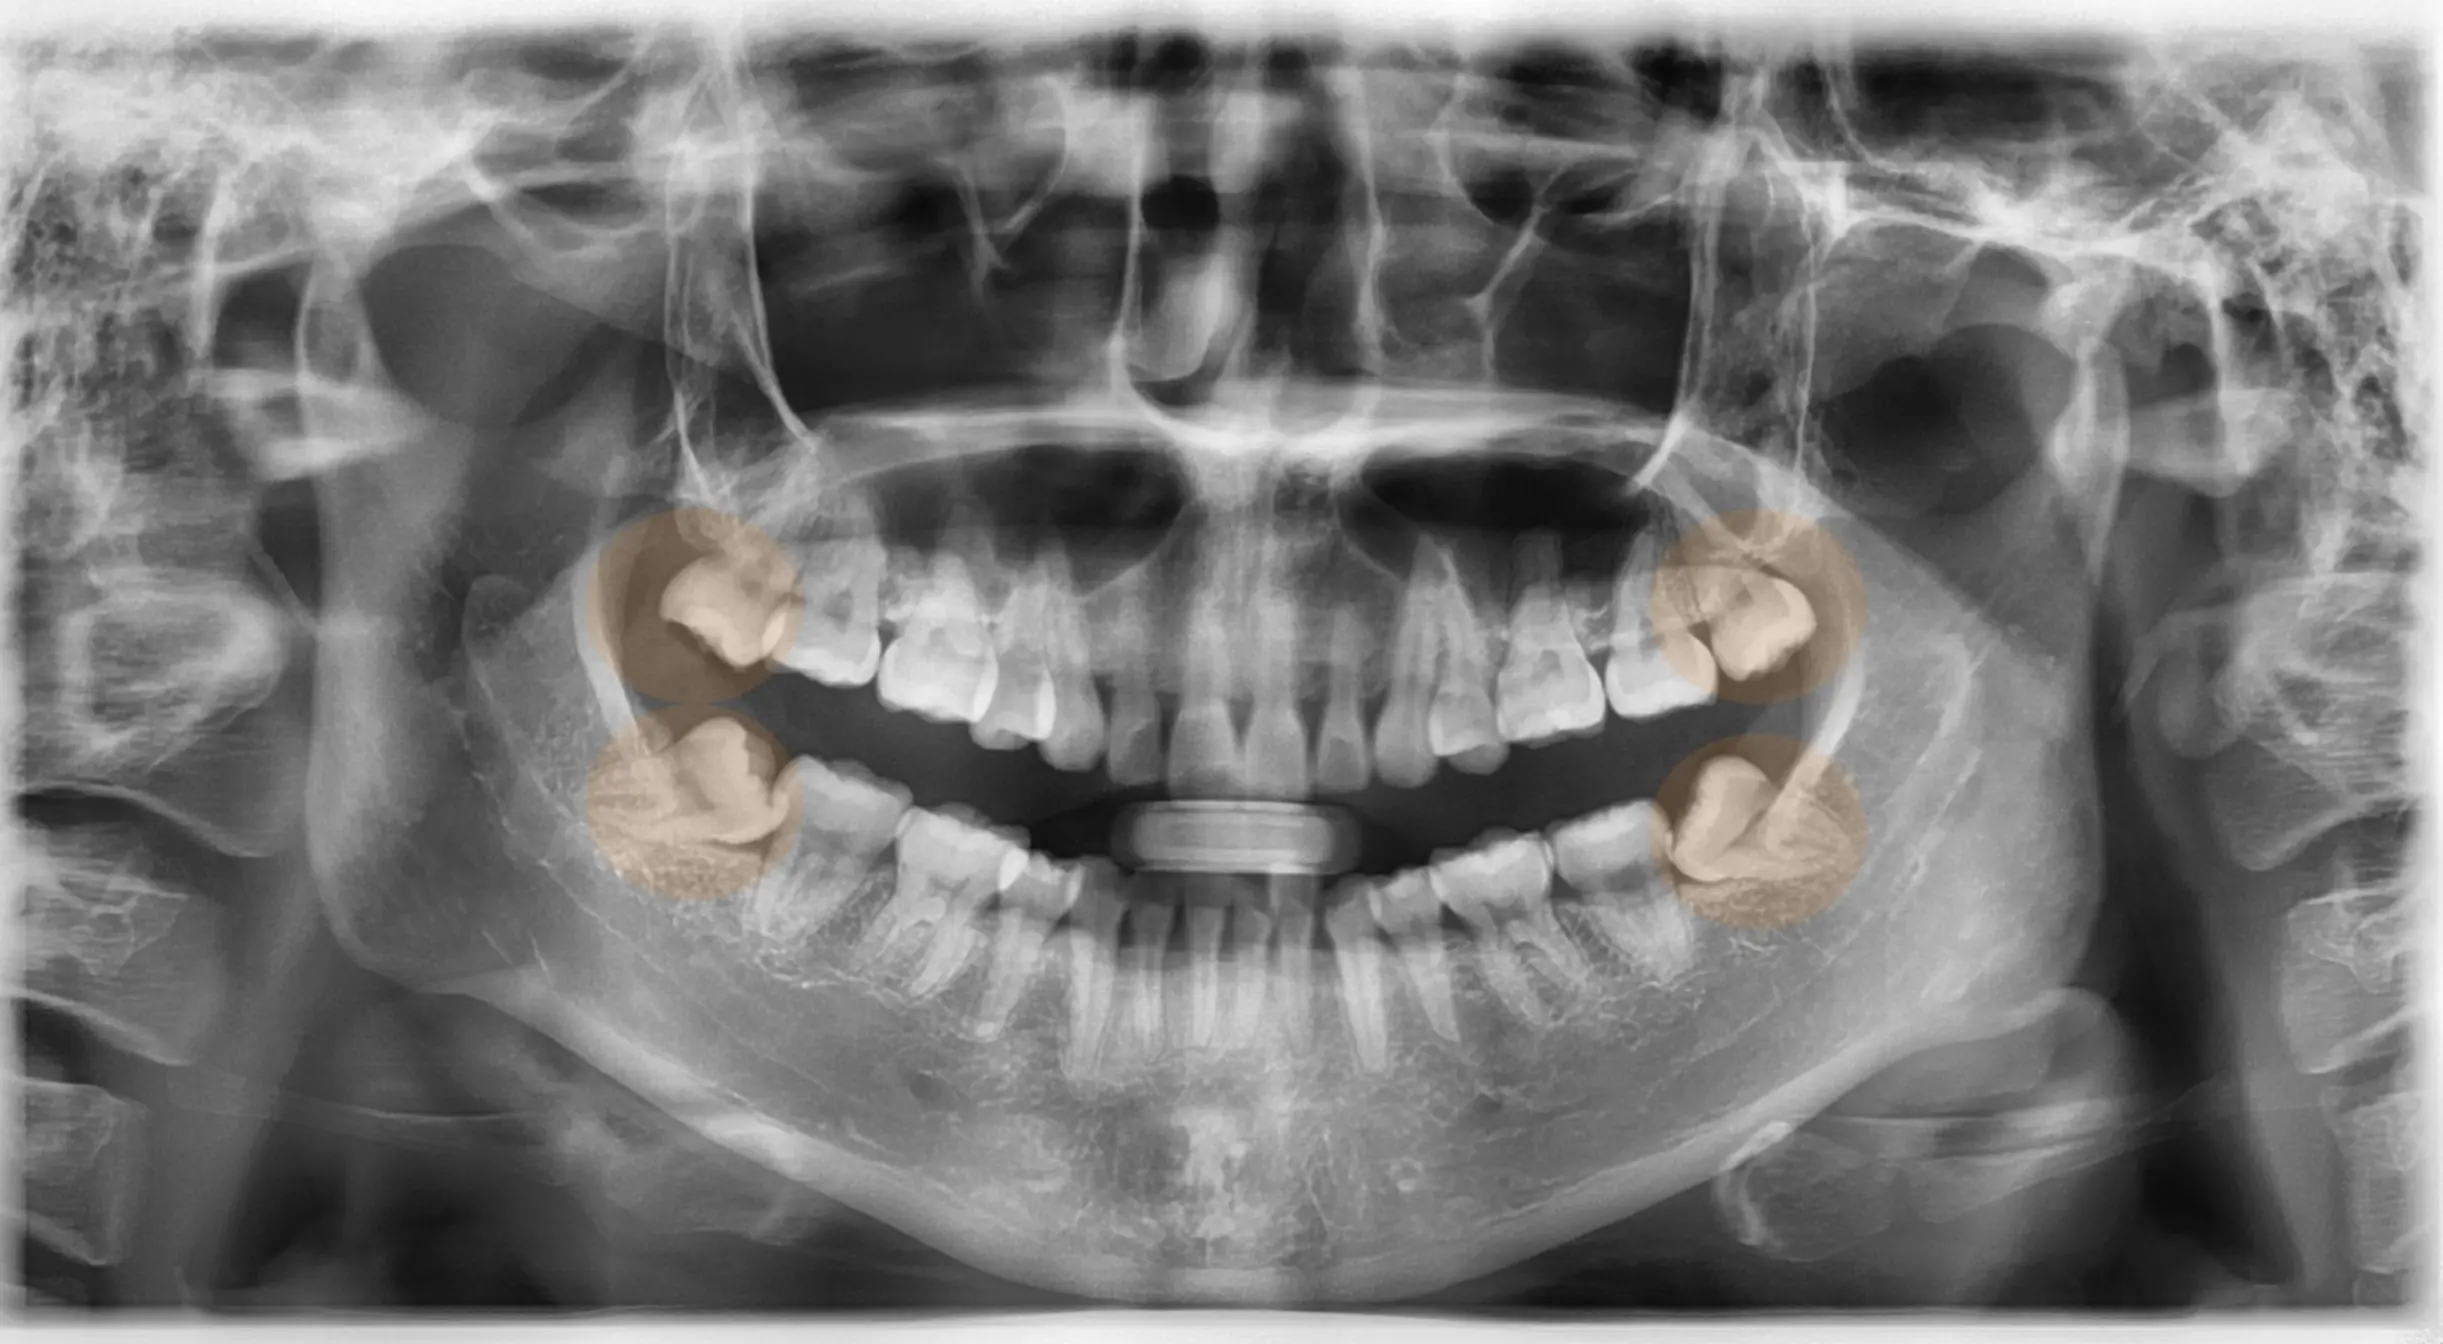

Step 1 – Consultation & X-Ray

Detailed examination for personalized treatment

We check the position of your wisdom tooth using digital X-rays and a complete oral examination to recommend the safest and most effective removal solution.